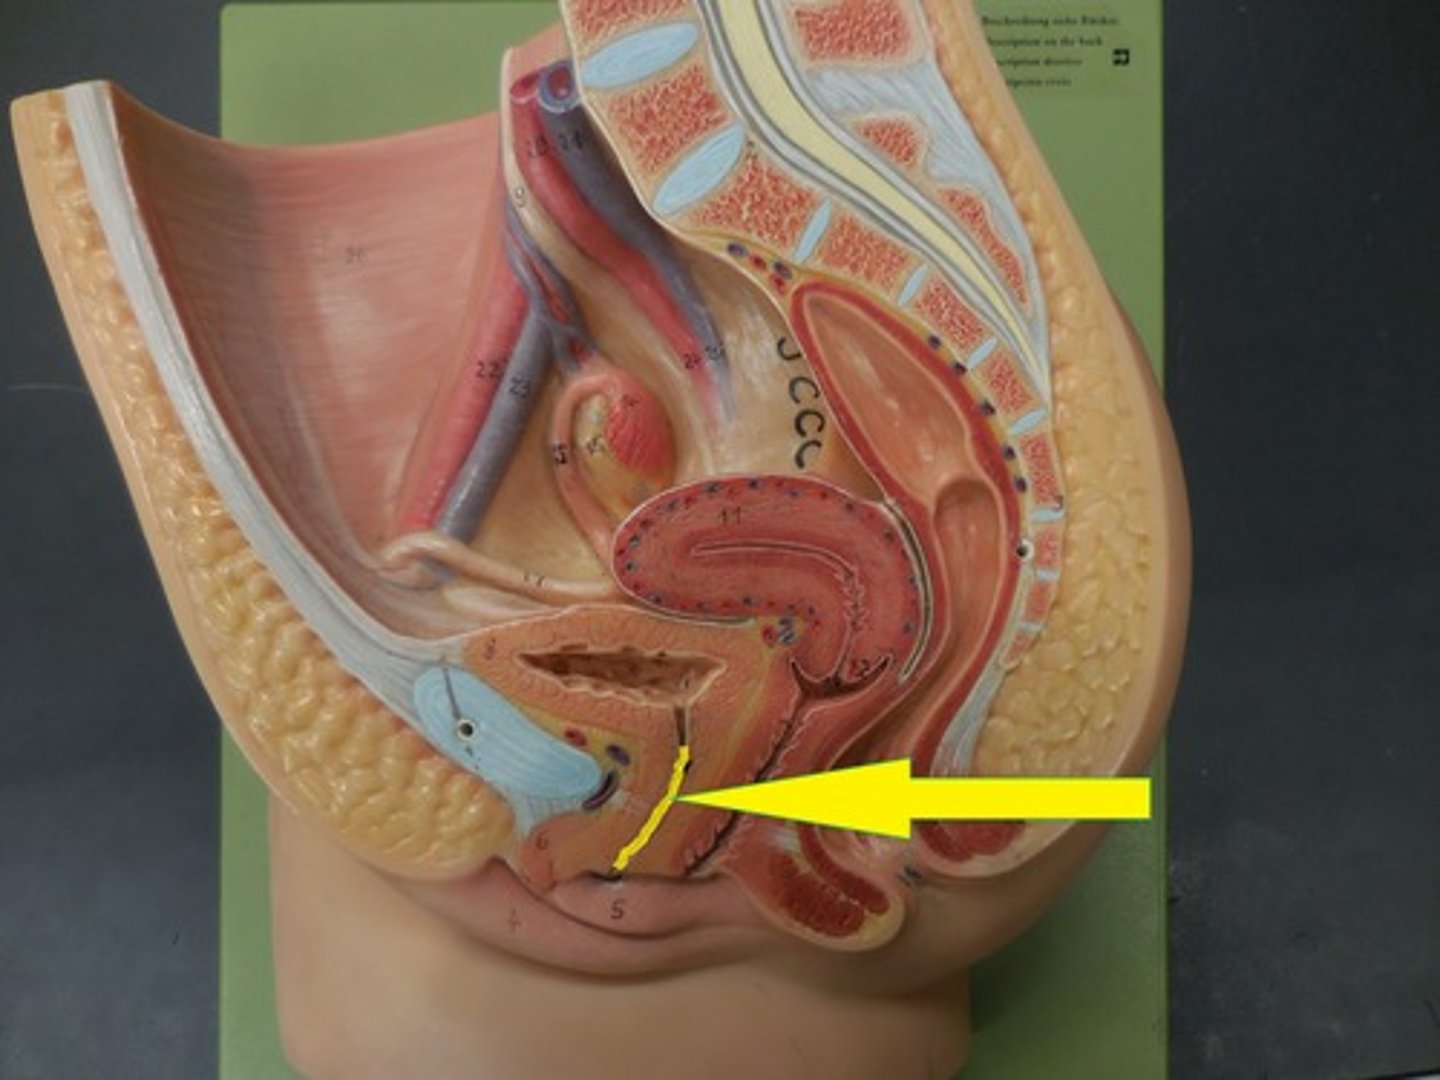

urinary bladder

urinary bladder

detrusor muscle

layer

internal urethral sphincter

bladder neck

external urethral sphincter

ureteric orifice

trigone of bladder

rugae

Urethra